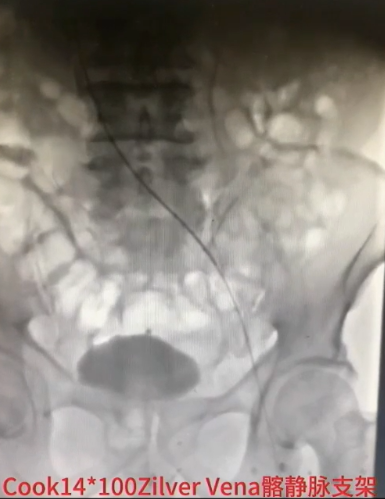

手术过程(五):复查造影见髂总静脉处仍狭窄,与家属沟通后,同意置入支架。引入髂静脉支架,定位准确后,谨慎释放,12 mm×40 mm球囊扩张髂静脉支架。